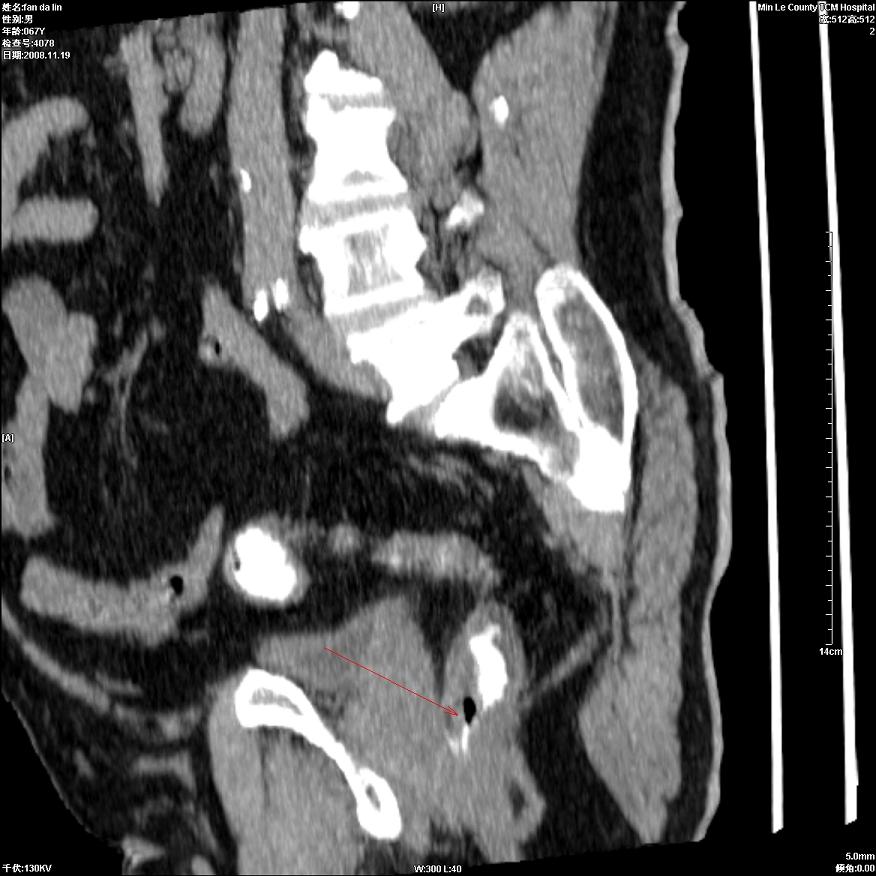

标题: CT16698:M67Y,看看直肠下端是不是病变 [打印本页]

标题: CT16698:M67Y,看看直肠下端是不是病变

粘膜皱壁,不除外内痔

直肠及乙状结肠管壁均增厚,考虑炎症.

直乙交界处肠壁不规则增厚,还是做个肠镜吧

只是肠壁局限性增厚,但难说明问题。